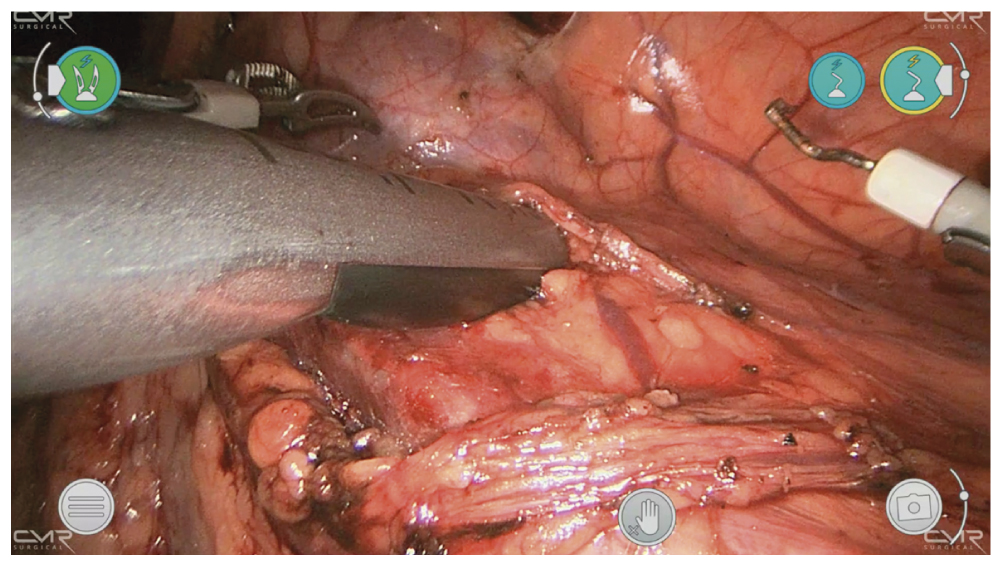

Для начала выполнялась мобилизация левого отдела ободочной кишки. После рассечения фасции идентифицировался мочеточник. Контактный лапароскопический ультразвуковой зонд — дополнительный инструмент, который может помочь в определении локализации камней. При размещении датчика на передней стенке мочеточника определено местонахождение камня внутри мочеточника (рис. 2).

Рис. 2. Интраоперационное контактное ультразвуковое исследование с целью поиска расположения камня внутри просвета мочеточника.

Fig. 2. Intraoperative contact ultrasound examination for locating the stone inside the ureteral lumen.